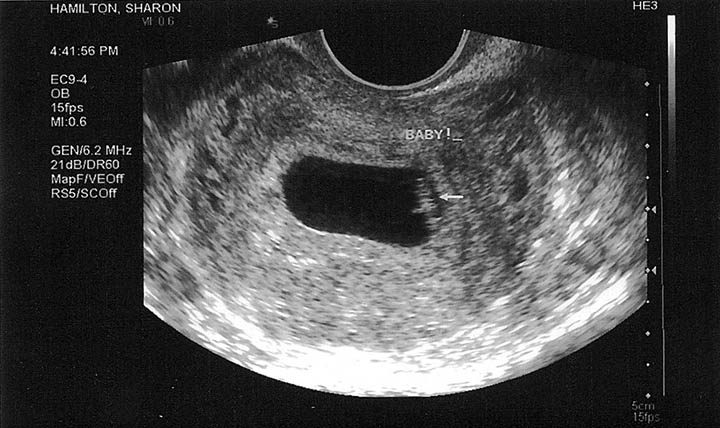

Bebeğin ultrason görüntüsü: